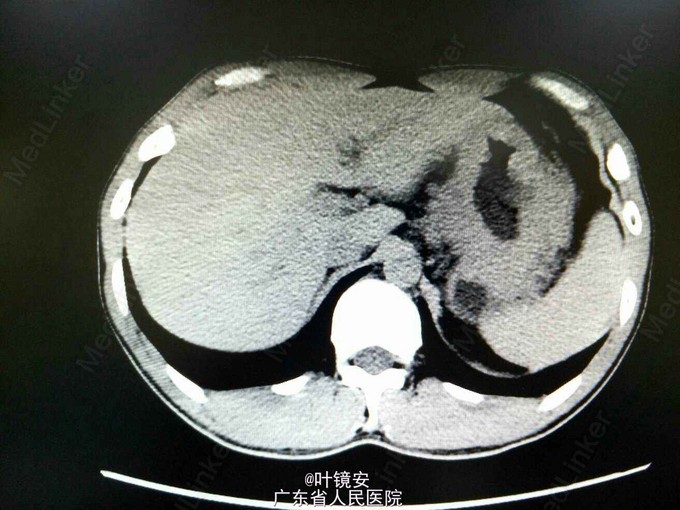

查体:生命体征平稳,心肺无特殊,左上腹部轻压痛,无反跳痛。辅助检查:全腹CT检查提示贲门—胃底—胃体癌可能性大,并侵犯浆膜层以及胃周淋巴结转移。病理玻片会诊提示低分化腺癌(Lauren分类,弥漫型)。肿瘤指标未见明显异常。